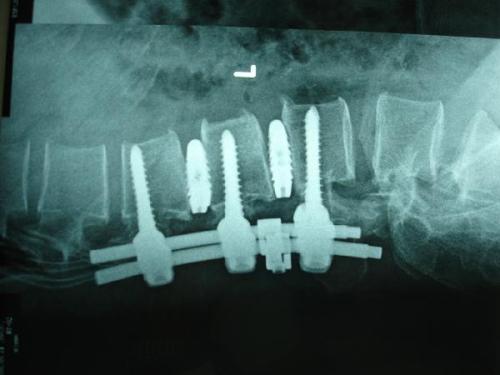

- 手术:有些椎间盘突出比较严重,引起了马尾神经综合征,或者椎管狭窄。有些因为反复发作,保守治疗无效,还有脱垂的椎间盘无法通过保守治疗恢复,则需要手术。手术的方法有微创和开放等多种!